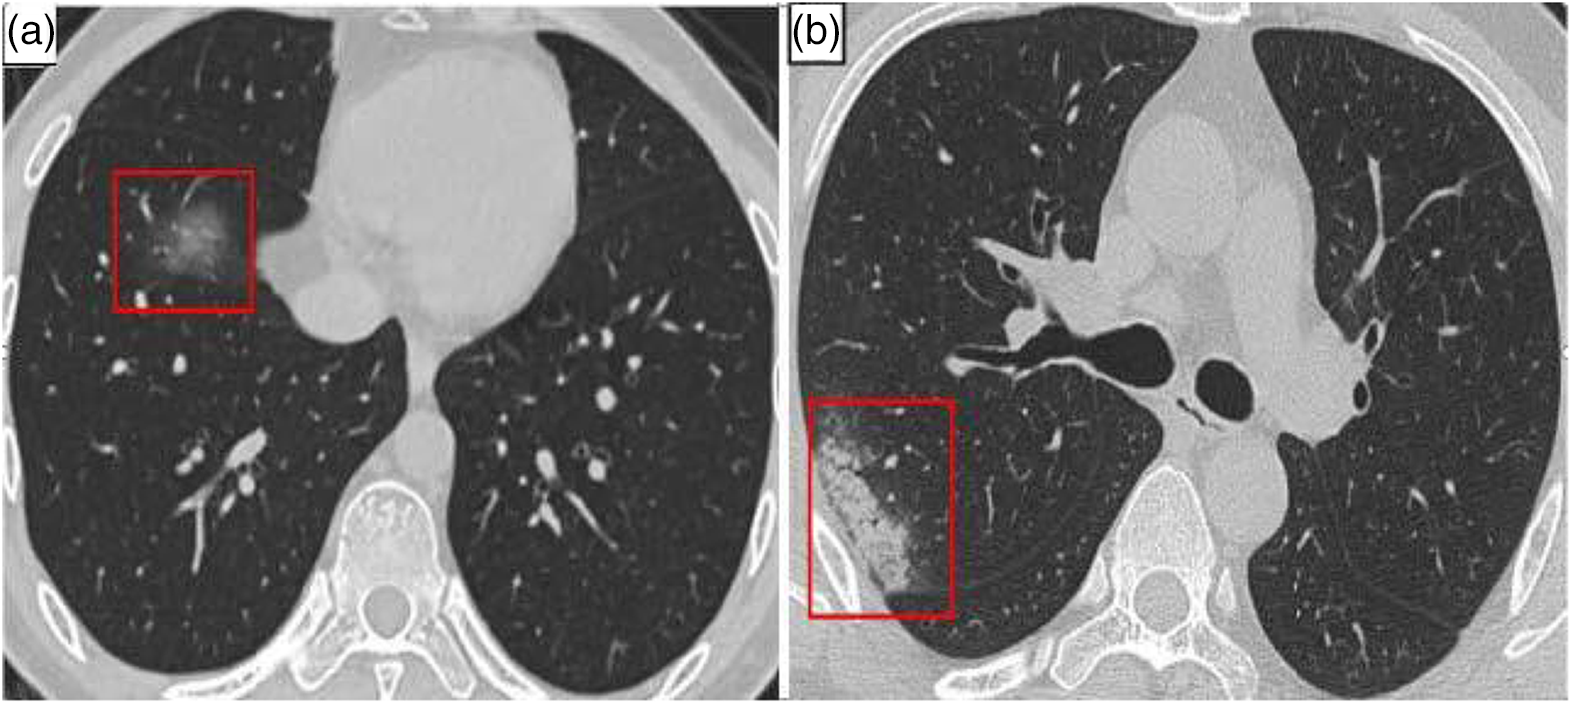

In individuals with COVID-19, consolidation (CL) and ground-glass opacities (GGO) are the most frequent lung CT abnormalities [10–12]. They are primarily located in the lung margin. The lesions eventually disappear to generate fibrotic streaks when the condition becomes better [13–19]. The majority of patients also exhibited imaging characteristics such as thickened bronchial vessels and interlobular septa [20,21]. The patient’s lungs’ CT imaging results are shown in Fig. 1.

Figure 1: COVID-19 patient’s CT of lungs. (a) GGO (in red box) (b) Consolidation (in red box)